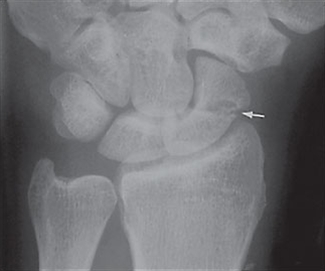

- Positivt fund på røntgen eller MR